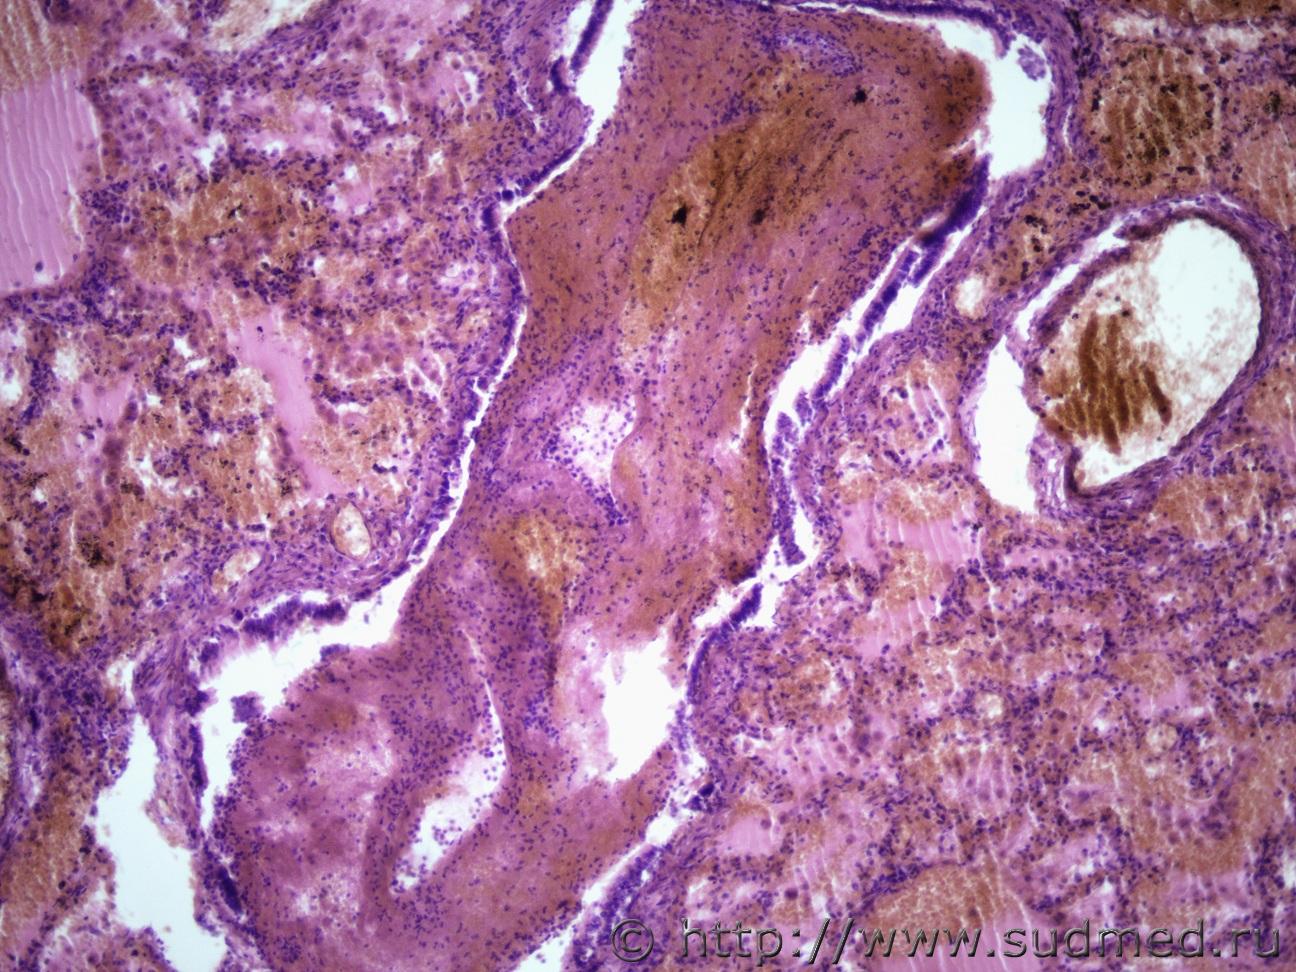

Подскажите как назвать данную пневмонию. По закону парных случаев, на данный момент у меня два разных случая с одинаковой морфологией. В морфологии в альвеолах эозинофильное содержимое, слущенные альвеолоциты, гигантские, многоядерные клетки, выраженный геморрагический компонент, местами немного лейкоцитов, свертки фибрина. Обширные свертки в бронхах. Очень похоже на вирусную, но как ее может назвать морфолог? Судебная медицина - Прикрепленное изображениеСудебная медицина - Прикрепленное изображениеСудебная медицина - Прикрепленное изображениеСудебная медицина - Прикрепленное изображение

Интерстициально-десквамативная.

+ местами похоже на гиалиновые мембраны и в капиллярах межальвеолярных перегородок встречаются мегакариоциты.

По-видимому,непосредственная причина смерти ИТШ.

Да, совершенно верно. Признаки РДСВ есть

ОВБИ осложненная серозно-гнойной пневмонией, геморрагическим отеком, двс-синдром.